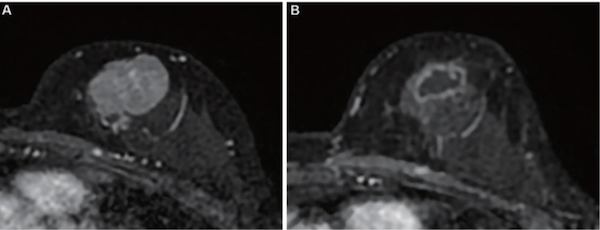

55-year-old patient with triple-negative breast cancer (TNBC) from training set

Liang et al.’s AJR manuscript included patients with TNBC undergoing NACI and who underwent breast MRI including dynamic contrast enhancement before treatment and after the first treatment cycle (i.e., early NACI), including a single-center training set of 90 women (mean age, 49 years; January 2018 to September 2024) and an external test set of 29 women (mean age, 46 years; date range unavailable) from publicly available trial data. Two radiologists evaluated MRI features, including percentage enhancement (PE) reduction, representing semiquantitative assessment of relative expansion of intralesional nonenhancing components after early NACI. A model for predicting pCR on definitive surgery after NACI completion was constructed in the training set using independent predictors from multivariable logistic regression analysis and was evaluated in the external test set.

Ultimately, Liang and colleagues’ model constructed to predict pCR in patients undergoing NACI for TNBC combined tumor unifocality on pretreatment MRI and early tumor shrinkage ≥ 37% and percentage enhancement reduction on MRI performed after one cycle. In an external test set, the model achieved AUC of 0.88, sensitivity of 74%, and specificity of 90%.